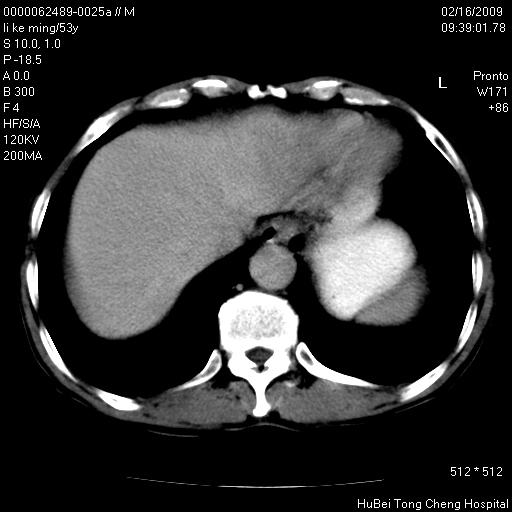

以下是引用卜一在2009-2-16 16:13:00的发言:[br]胰胆管扩张,末端明显狭窄 梗阻,胰头及十二指降段壶腹部结构紊乱。多考虑:十二指降段壶腹部癌!

以下是引用zsl6918在2009-2-17 8:48:00的发言:[br]符合胰头癌侵犯十二指肠。